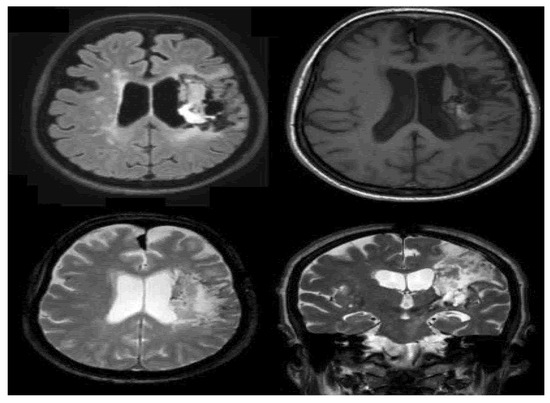

2. Case Description